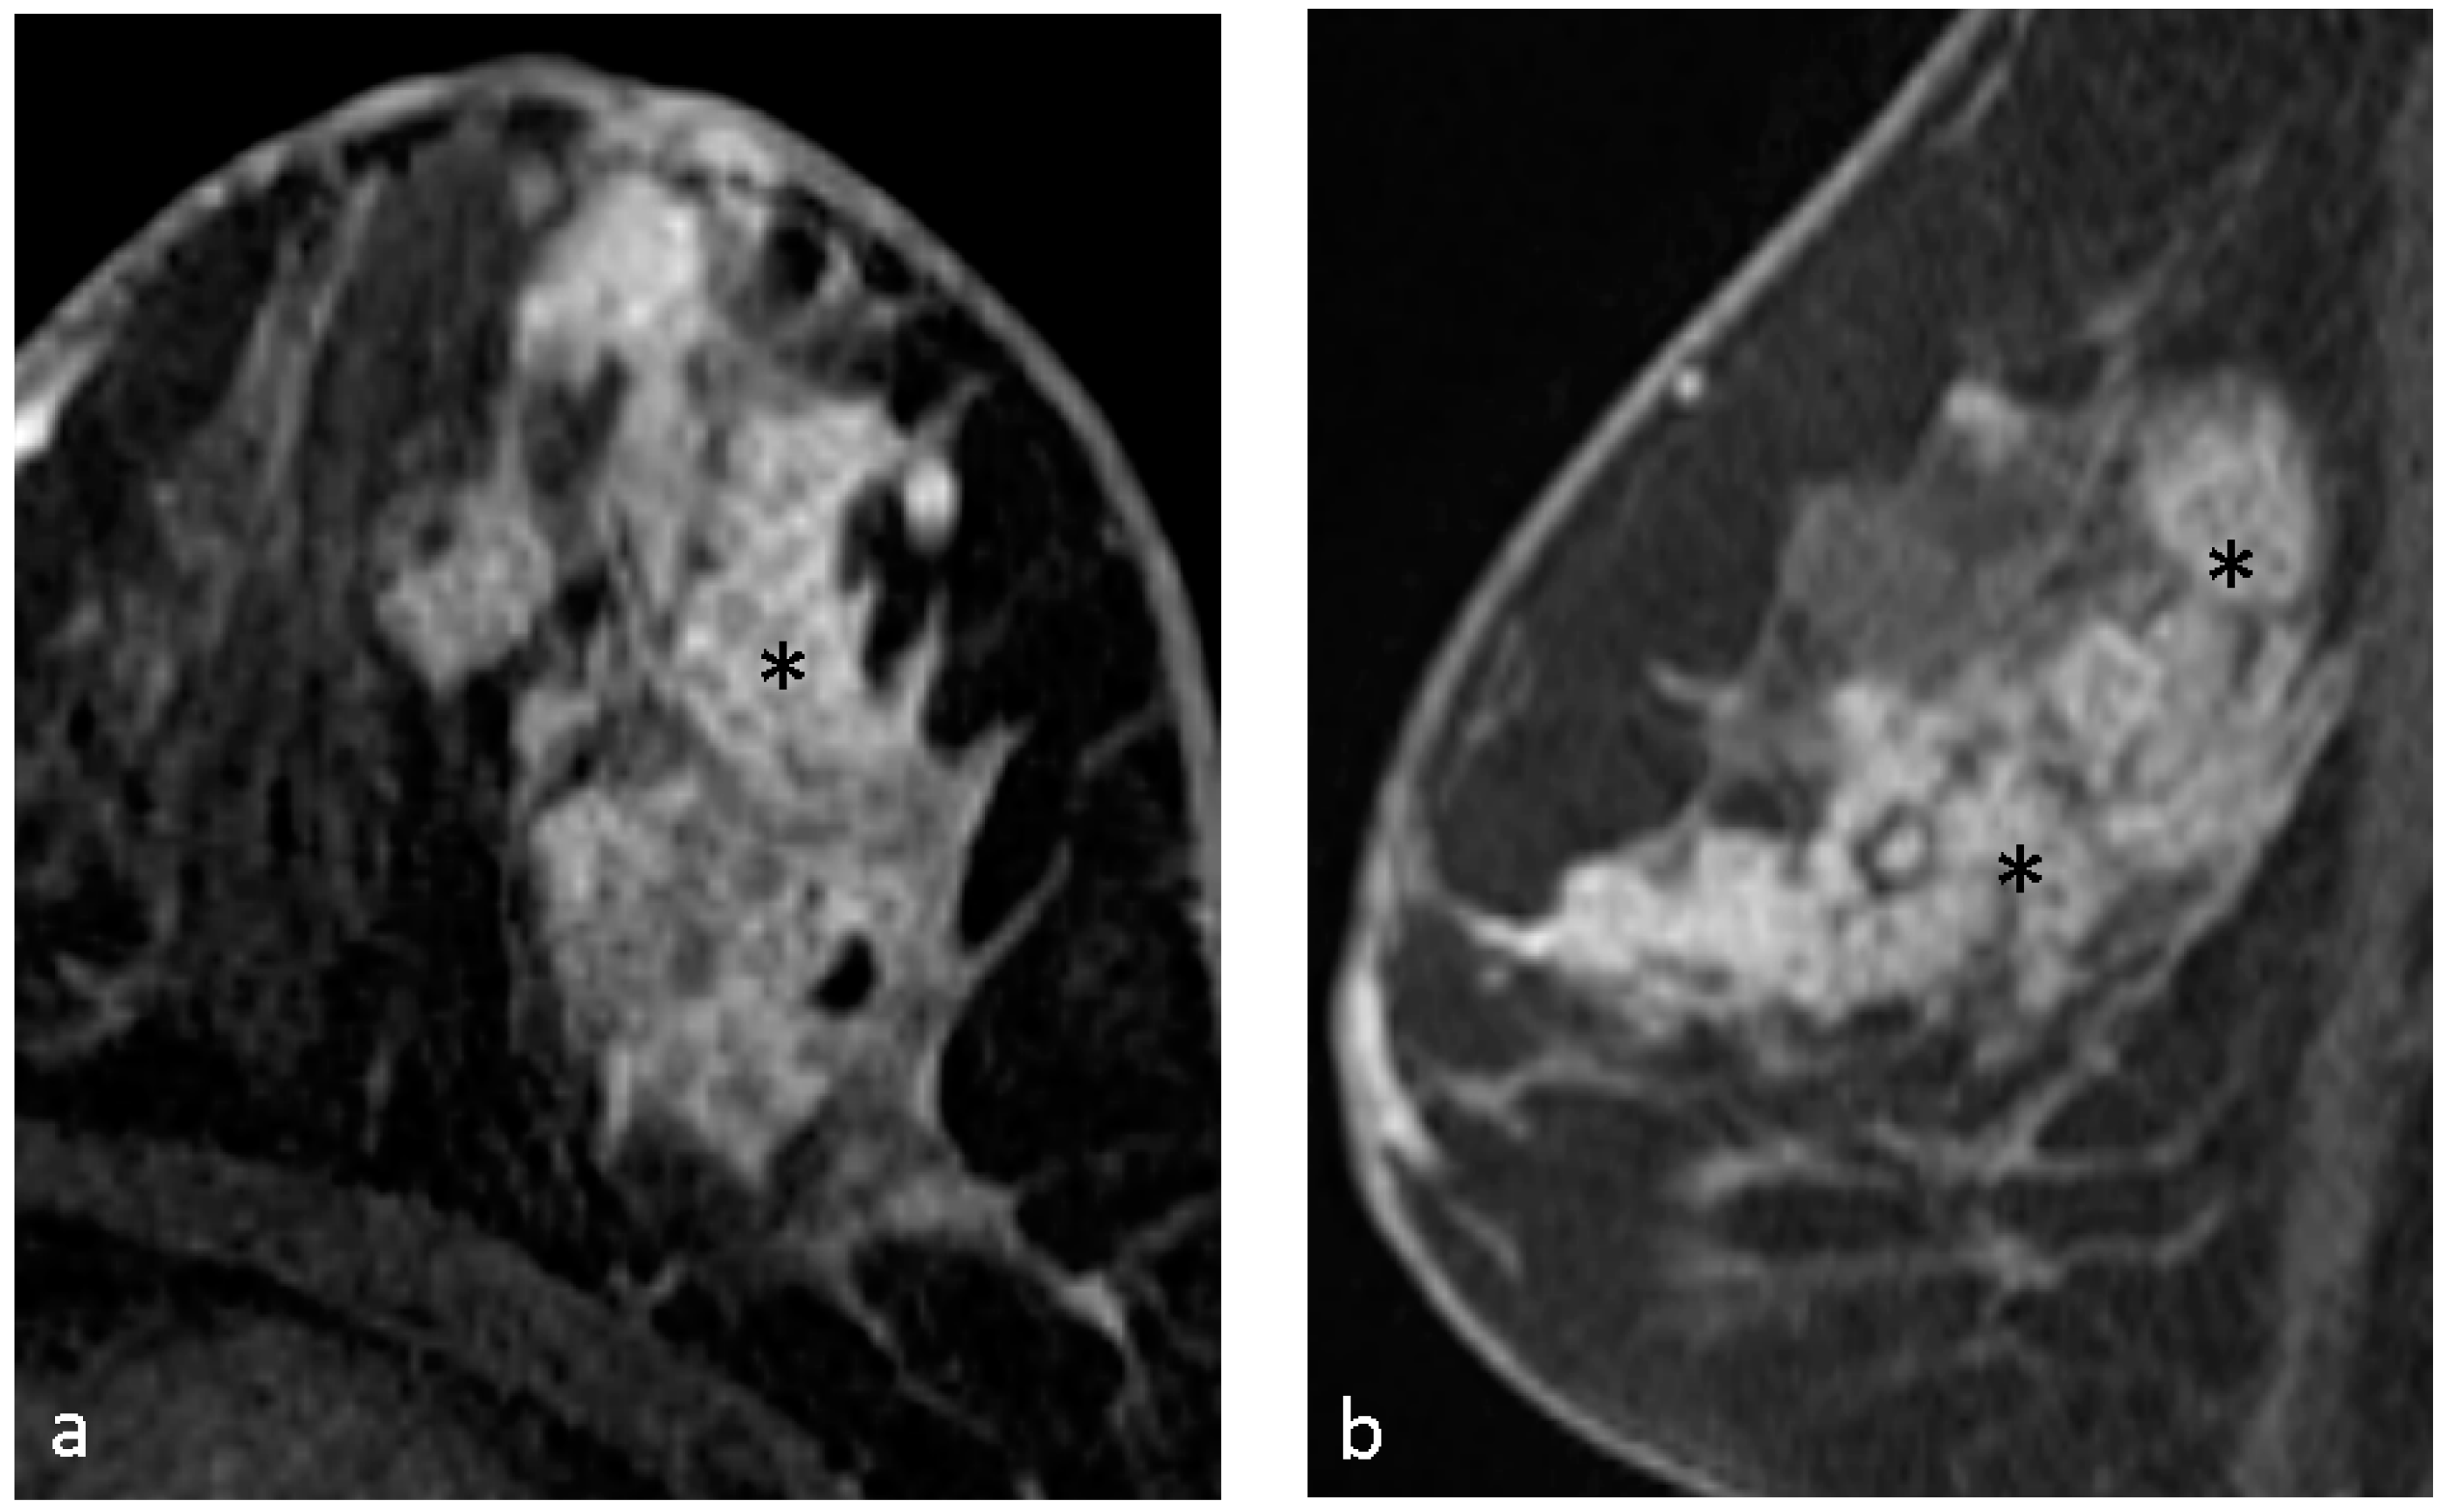

| Clustered ring enhancement | 31 (53.4%) |